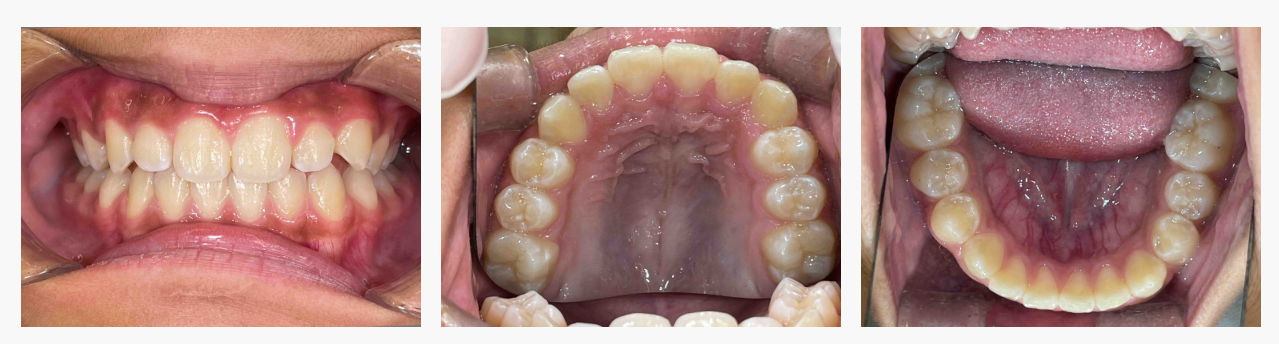

▼ After(治療後)

◆ 治療の結果

マイオブレイスによる機能改善と成長誘導により、

・ガタガタの改善

・上の前歯の突出の軽減

・口元のバランス改善

・鼻呼吸の定着、正しい舌位置の獲得

など、多面的な改善がみられました。

歯を強制的に動かすのではなく、お子さま自身の成長力を活かす小児矯正ならではの良好な結果です。